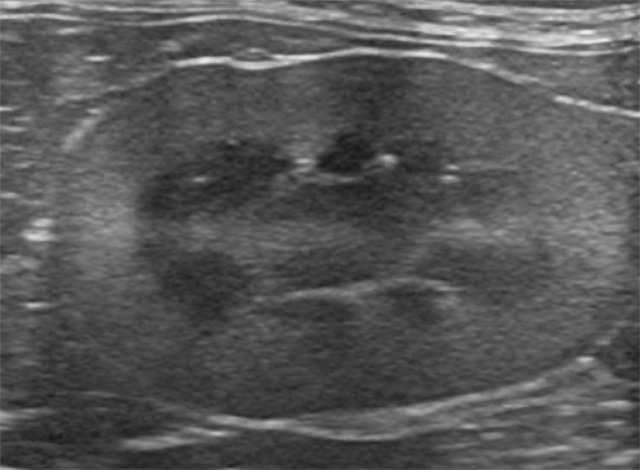

当院では、単に「数値が高い」で終わらせません。高性能エコーや尿検査、血圧測定を組み合わせ、「なぜ腎臓に負担がかかっているのか」という根本原因(尿管結石や腎腫瘍など)を徹底的に調査します。原因に応じたアプローチを行うことで、残された腎機能の温存と全身状態の改善を目指します。

血液検査の数値(SDMAやCREなど)の裏に隠された、結石、構造的異常、腫瘍などを見逃しません。高性能な超音波検査機器を駆使し、腎臓とその周辺の細かな変化を視覚的に捉えます。